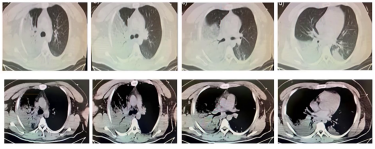

影像学检查:

1、大叶性肺炎

优先考虑此诊断,支持证据包括:青年男性起病急、病程短;以咳嗽、发热等呼吸道感染症状为主,伴痰中带血、乏力(符合社区获得性肺炎特点);胸部CT见右肺大片实变影及支气管充气征;入院时已出现呼吸衰竭、多脏器功能不全征象,需警惕重症肺炎。目前需进一步明确病原菌(如肺炎链球菌、克雷伯菌等)。

2、干酪性肺炎(结核相关)

需鉴别考虑,支持点为青年男性(结核好发年龄)、咳嗽/发热/痰中带血等表现、胸部CT多叶段实变影;但起病时间短,不符合结核的生长规律,暂不优先考虑。